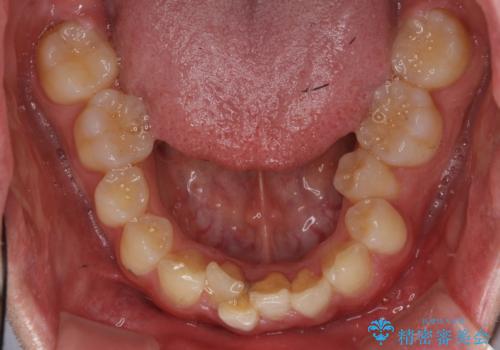

左下の奥歯を後ろに移動して、中に入ってすれちがっていた小臼歯を並べました。

奥歯を後ろに移動させるために、矯正用のミニスクリューを用いました。(インプラント矯正)